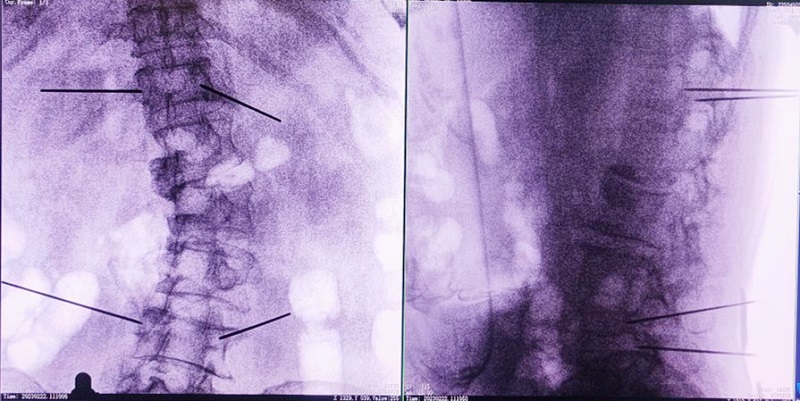

(3)根据设定好的的位置和入针方向,植入引导针;

(4)所有引导针植入完毕后,沿引导针方向进行椎弓根及椎体置管,建立通道;

(5)沿通道注入骨水泥,恢复椎体高度,并观察其扩散情况,达到满意效果后,停止注入骨水泥。